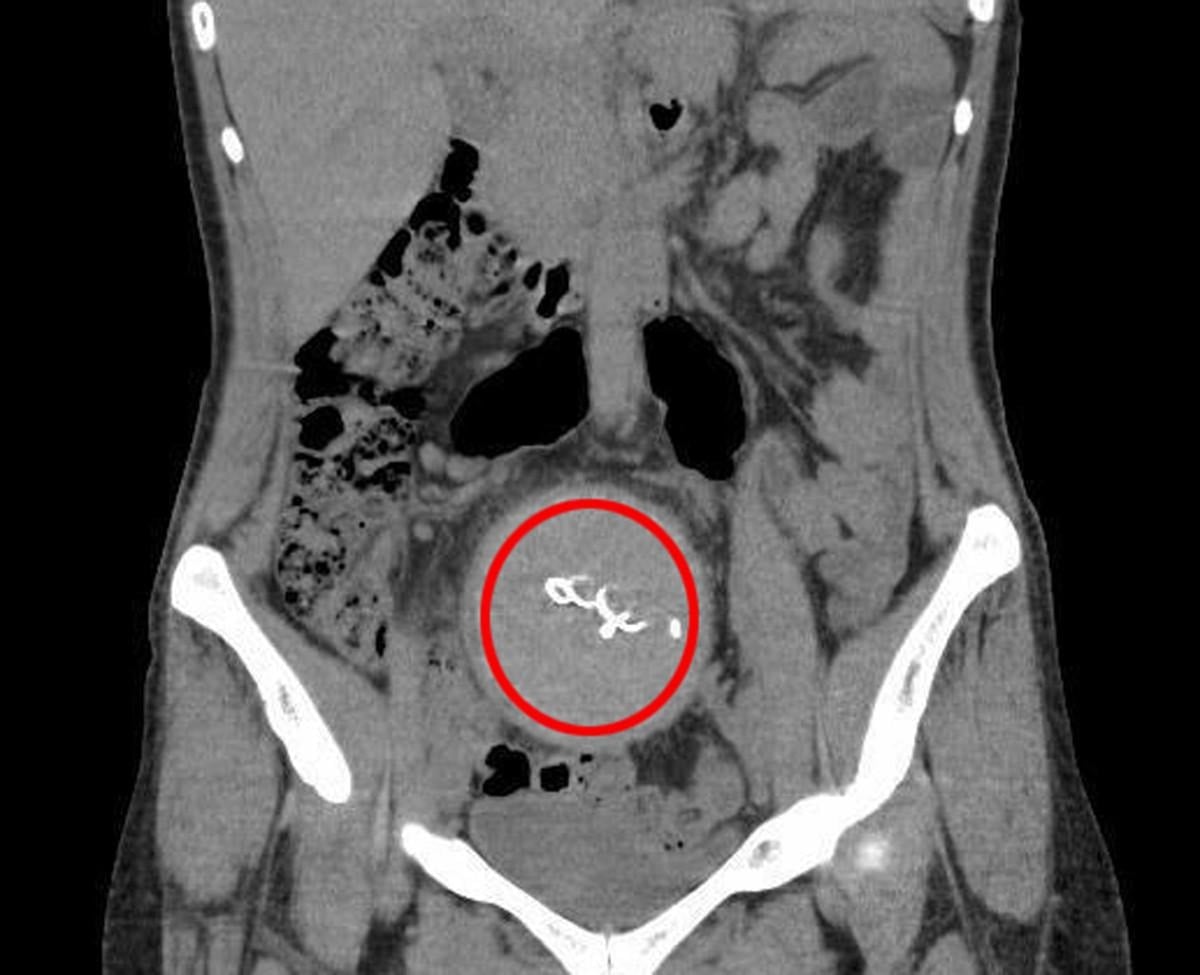

Burada yapılan kontrolde doktor acil tomografi çektirmesini istedi. Çekilen tomografide, Y.S.’nin vücudunda doğum sonrası unutulan sargı bezi görüldü.

Y.S.'nin karnında unutulan yaklaşık 30 santimetre uzunluğundaki gazlı bez ameliyatla çıkarıldı. Y.S., hastane ve doktor hakkında hukuki süreci başlatması için avukatı Hasret Baş’a başvurdu.